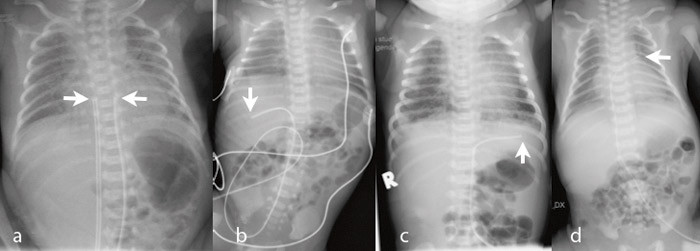

278 navlevenekatetre og 99 navlearteriekatetre ble innlagt hos totalt 298 nyfødte. 78 (26 %) fikk både arterie- og venekateter. Figur 1 – 3 viser røntgenbilder med ulike kateterposisjoner. I ett tilfelle fikk pasienten utilsiktet to navlevenekatetre (fig 2a) og i to tilfeller fant begge katetrene veien til samme navlearterie (fig 2b og 2c). Indikasjonene for innleggelse var prematuritet hos 156 (52 %), asfyksi hos 41 (14 %), infeksjon hos 37 (12 %), respirasjonsbesvær hos 24 (8 %), misdannelser hos 12 (4 %) og andre indikasjoner hos 28 (9 %).

Tabell 1 angir kateterposisjonene. Av navlearteriekatetrene var 45/99 (45 %) primært riktig plassert, og 77/278 (28 %) av venekatetrene. Navlearteriekatetre lå oftere for lavt (44/99; 44 %) enn for høyt (10/99; 10 %) (p < 0,001). Tilsvarende lå flere navlevenekatetre for lavt (126/278; 45 %) enn for høyt (75/278; 27 %) (p < 0,001). Hos 14 (5 %) av venekatetrene og seks (6 %) av arteriekatetrene var det krøll på kateteret (fig 3). For venekatetrene lå krøllen hos 11 i ductus venosus og hos tre i portveneområdet. For arteriekatetrene lå krøllen hos alle i aorta.